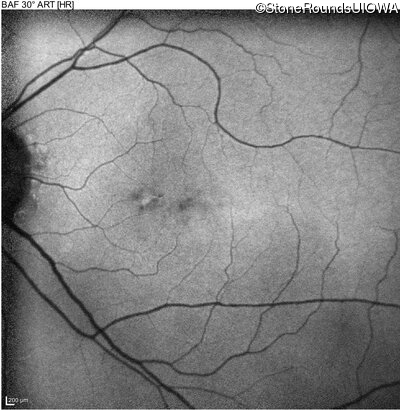

The clinical features favoring the diagnosis of RP1L1-associated occult macular dystrophy include: reduced acuity with a near-normal ophthalmoscopic appearance, a history of normal acuity in childhood; and, a "moth-eaten" appearance of the macular ellipsoid zone on OCT.

Age at visit: 77 years